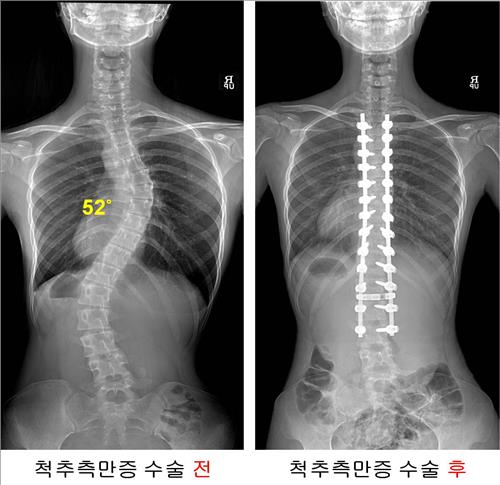

측만증은 뒤에서 봤을 때 척추가 일자로 서 있지 않고 옆으로 휘어진 상태를 말한다. 측만증의 90%는 그 원인을 잘 모르는 '특발성 측만증'이다. 어렸을 때는 척추가 휘어진 사실을 잘 모르고 지내다가 10대 초반에 많이 발견하는데, 45∼50도 이상 휘었을 때 수술하는 게 일반적이다.

척추의 휘어진 각도는 수술 전 평균 57.3도에서 수술 후에는 11.9도까지 펴져 약 79%의 교정률을 보였다.